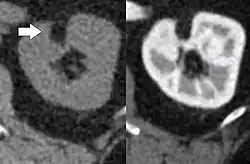

| Angiomyolipoma in both kidneys (arrows) in computer tomography. The tumours are hypodense (dark) due to fat content. | |